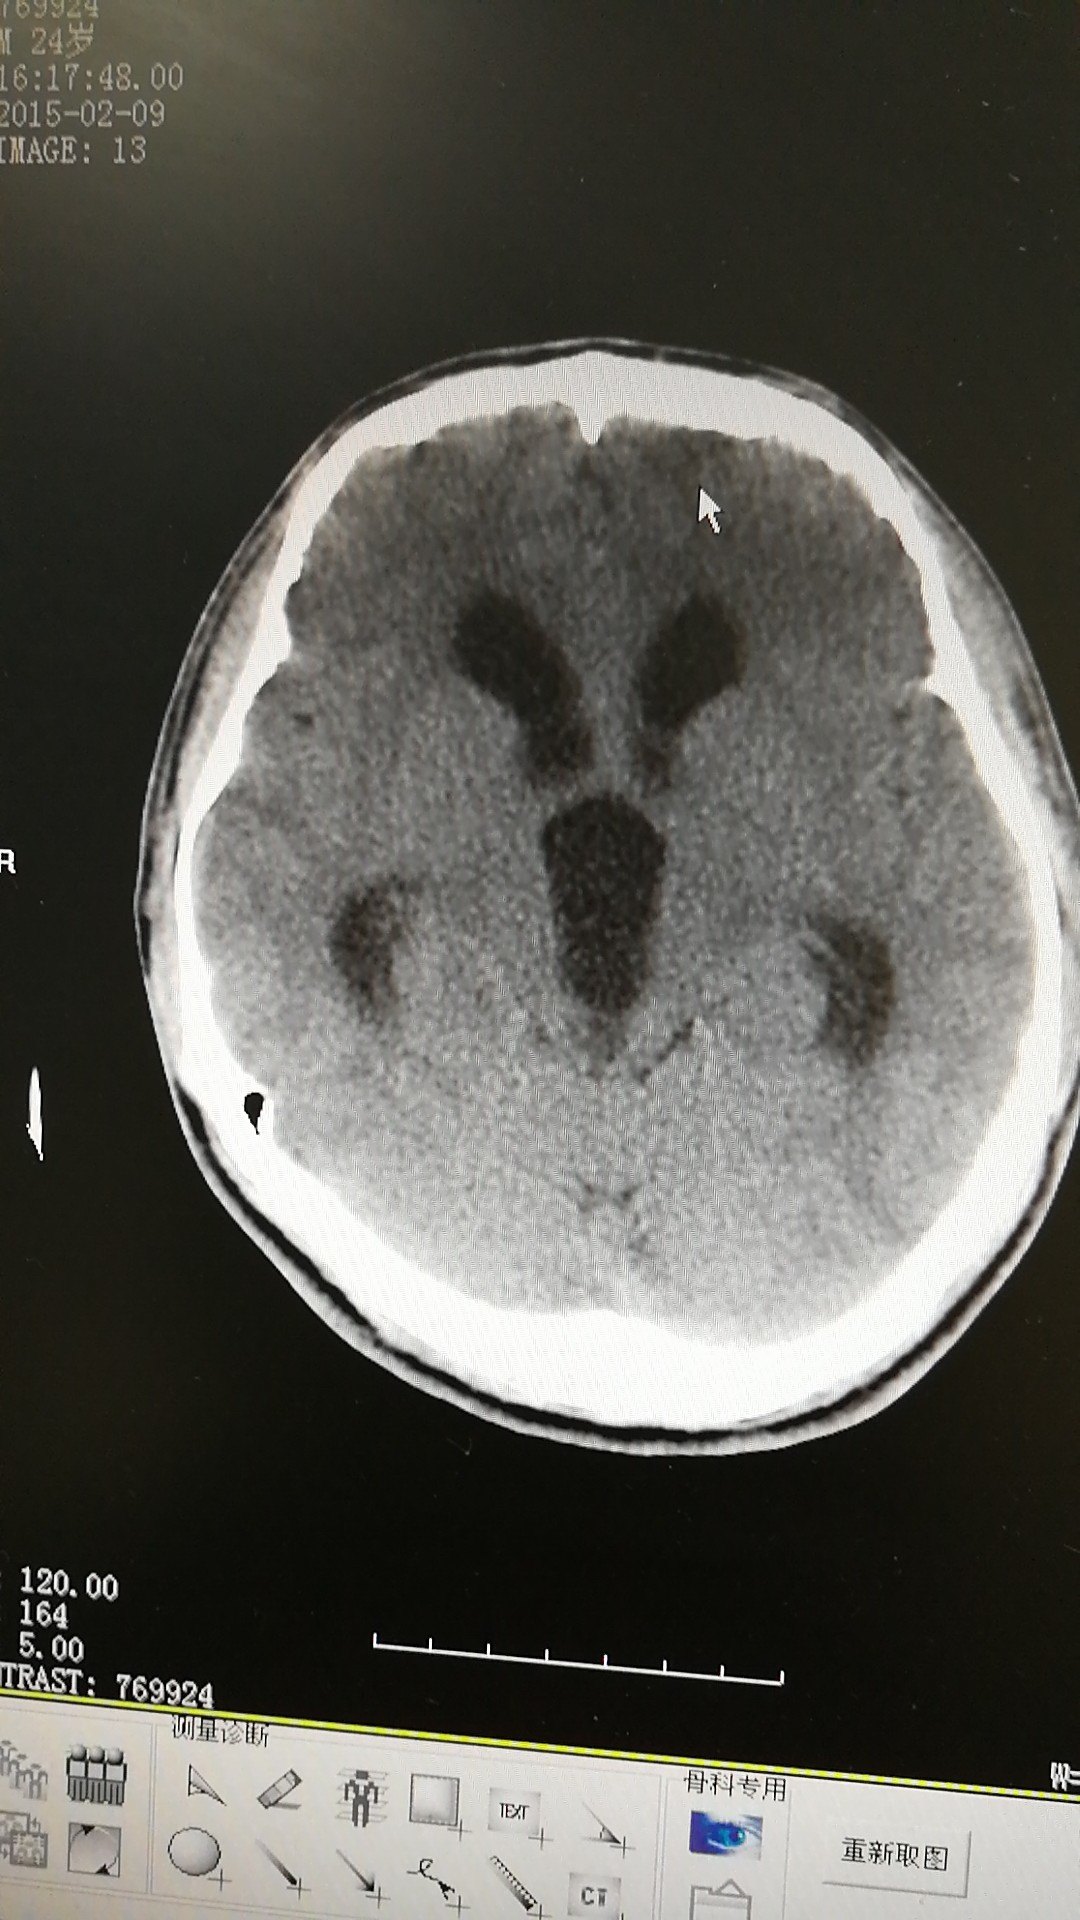

手术后可以明显改善症状,效果明显.脑积水ct显示:侧脑室,三脑室扩大

脑积水ct显示:侧脑室,三脑室扩大有症状的脑积水应该及时手术治疗.